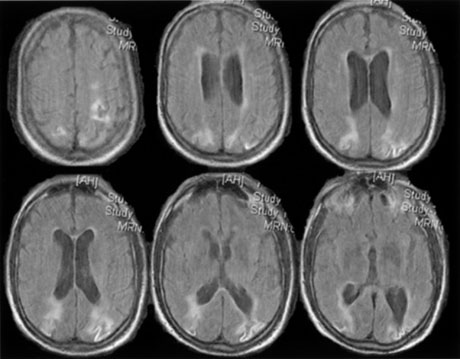

Fig. 15. Bilateral incomplete hemianopia. A 69-year-old man with decreased vision after prostate surgery. A. Fields show remaining central parafoveal vision with some sparing of inferior left quadrant. Note how the defect respects the vertical meridian. B. MRI shows bilateral medial occipital infarction, with sparing of the occipital poles, accounting for the macular-sparing bilaterally. (Courtesy of Dr. Lucia Vaina.)